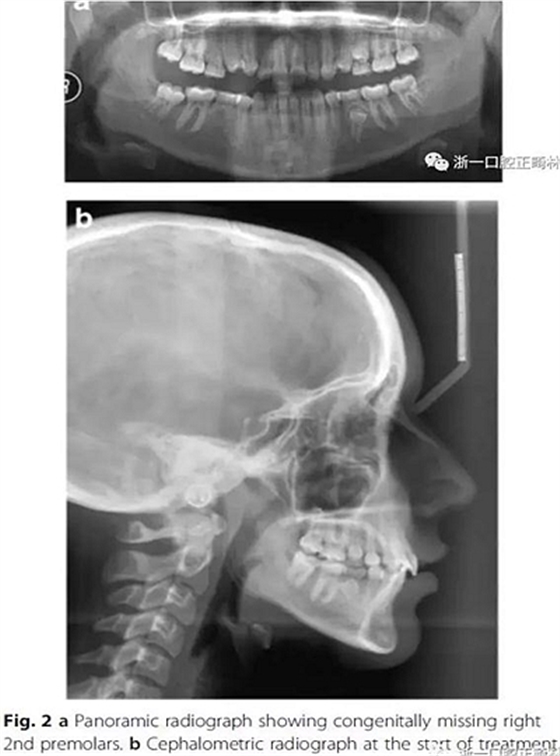

影像學(xué)檢查,右側(cè)第二前磨牙和所有第三磨牙先天性缺失;

頭側(cè)分析,骨性I類關(guān)系,高角型